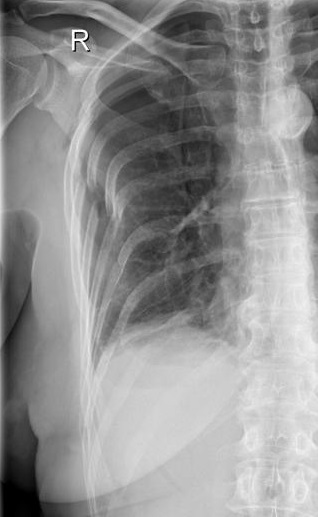

Image radiologique de

fracture de côte 4th , 5,6,7,8th droit du thorax .

Pneumothorax du poumon droit . Cliche de face PA

pulmonaire |

|

Même cas en OAD , les

fractures à diplacement angulaire et de glissement

être en vue très nette . |